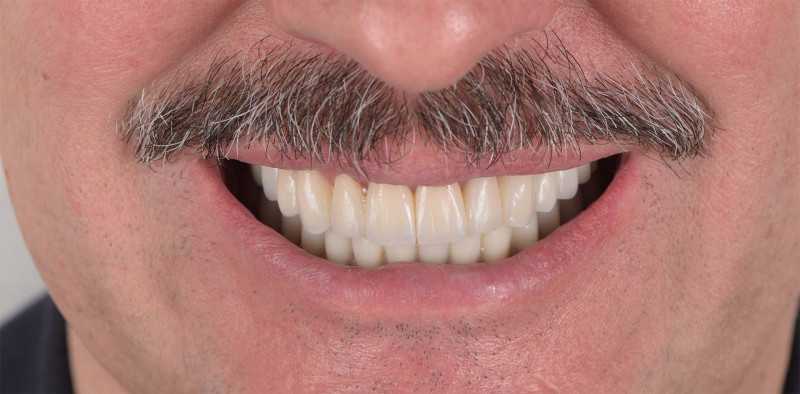

9 работ в портфолио

Брызгалин Михаил Андреевич принимает в Стоматологии THE DENT (ЗЕ ДЕНТ) в Москве. Главный врач, стаж 11 лет. Специализируется на ортопедии, по которой клиника оказывает 15 услуг. Имеет 9 работ до/после в портфолио. Для уточнения дополнительной информации о специалисте или записи на прием можно позвонить по телефону